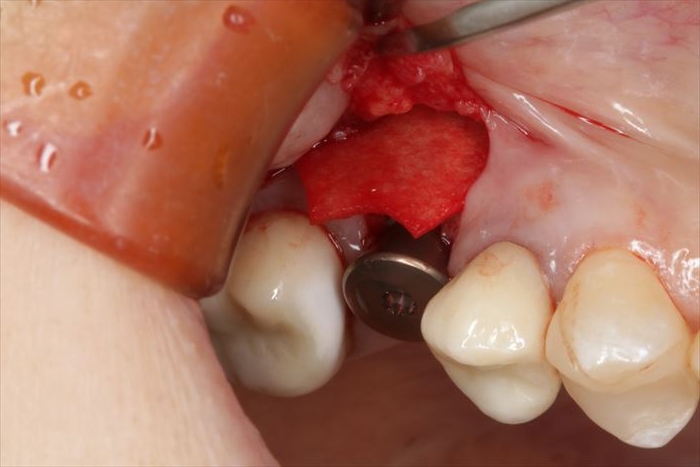

実際の骨の形を確認するために粘膜を剥離します。

頬側骨が少々足りない状況ですので、インプラント埋入後に骨増生処置(GBR)を行います。

スイス ストローマン社製のインプラントを用います。

BLT Roxolid φ4.1㎜ 長さ8㎜

インプラントの埋入を終えました。

インプラントを植えるためのパーツである挿入ジグを外しました。

ここから骨増生処置に移ります。

インプラント本体のスクリューホールの保護と歯肉の形態を整えるためにヒーリングキャップを用意します。

ヒーリングキャップを締結しました。

骨増生する部分の皮質骨表面に穴を開けて出血を促します。(デコルチケーション:皮質骨穿孔)

骨増生(骨造成)処置は血液が重要な役割を果たします。出血によって骨芽細胞が送り込まれます。